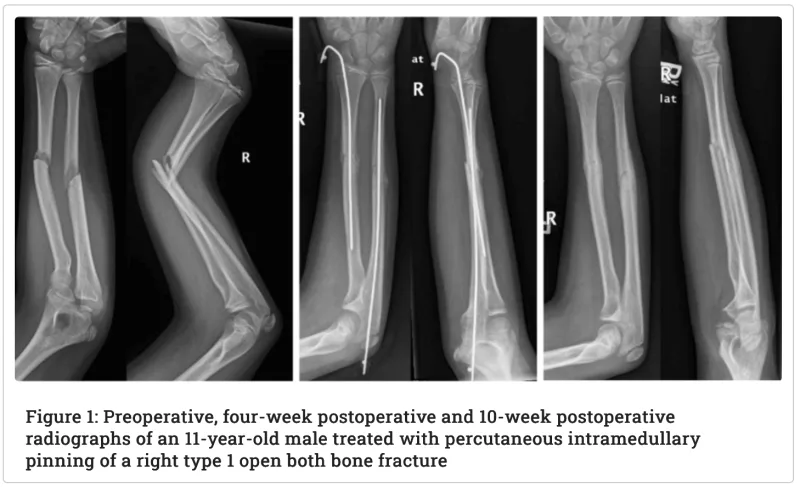

整形外科の入院の内訳は, 大腿骨頚部骨折の高齢患者さんが4人, 腰椎圧迫骨折が2人, そして前腕骨骨折の小学生が 1人でした.

午後には小学生の前腕骨骨折に対する鋼線髄内固定の臨時手術が実施されましたが、他業務のため見学はできず。電子カルテで無事終了したことを確認しました。

午後には小学生の前腕骨骨折に対する鋼線髄内固定の臨時手術が実施されましたが, 他業務のため現場監督はできず.

電子カルテで無事終了したことを確認しました.